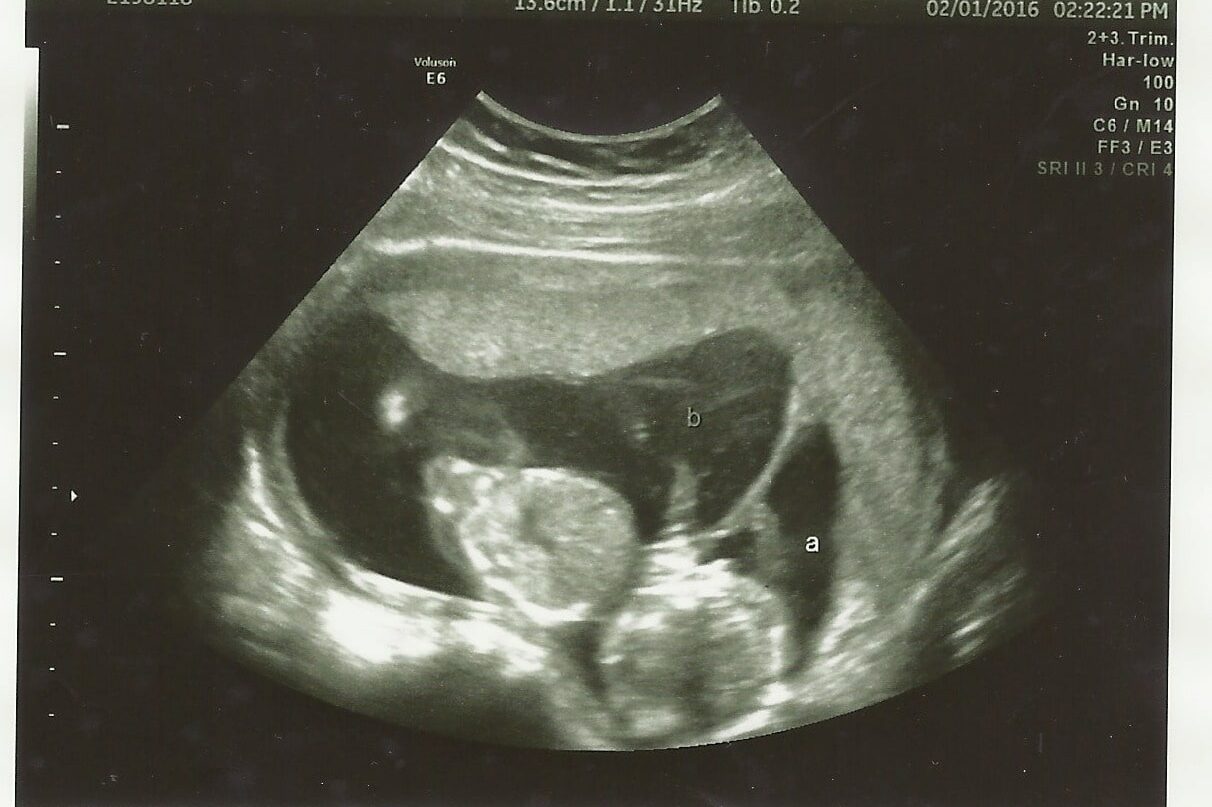

Didn’t know until we were 20 Weeks along. My doctors had done 2 ultrasounds and 3 heartbeat checks before then (at 6, 10, and 12 weeks)! We had done IVF so my hormone levels were even being checked.

∼ MHV

We did IVF and implanted one embryo. My last ultrasound with the IVF clinic was at 8/9 weeks, and still only one baby. At my first OB visit at 11 weeks, there was his twin. Never felt so blessed and terrified at the same time.

~ michy104